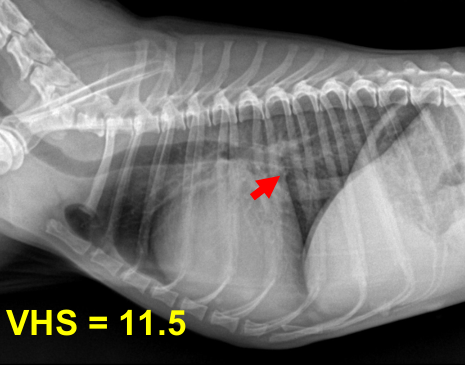

3기 (Severe : 좌심실까지 확실히 커짐)

1) 좌심방-좌심실 경계가 사라지고 흉벽과 가까워짐 ⇒ 우심부전까지 발생.

2) Tracheal elevation도 매우 뚜렷.